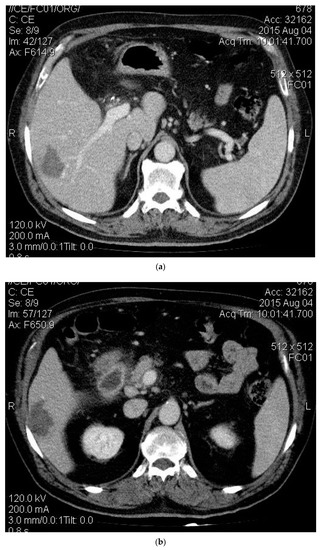

2. Case Presentation